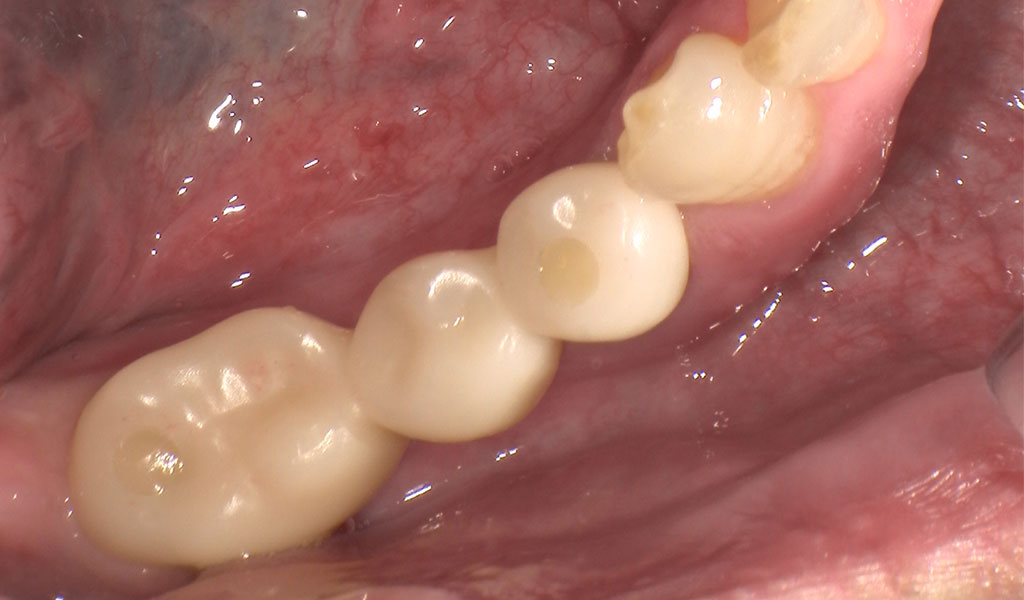

After1

手術にて、右下5番を抜歯後、右下5番,7番の骨にインプラントを埋め込みました。

インプラントと骨がしっかり結合するまで術後3ヶ月待ち、インプラントの上に人工の歯を被せる治療を行いました。

(右下5,6,7番)ジルコニアブリッジ(3本症例のうち、2本は上記インプラント代に含む):110,000円